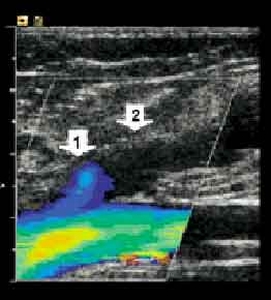

(1) 血流超音波 span>

可以發現手術後靜脈血流不會逆流, 倒流

可以發現手術後靜脈血流不會逆流, 倒流

(2) RFGSV (radiofrequency ablation greater saphenous vein) Closure <RFA>

「VNUS 通電閉合術」(VNUS closure)由美國加州聖何塞市的研究人員發明,醫生在病人足踝開一個針頭大小的孔,將一根導管經由小孔穿入病人腿靜脈內需去除的部份,然後用繃帶包紮腿部,將靜脈中的血全部擠走。在整個過程中,醫生一直用超音波掃描器密切觀察。

接著是經由導管前端輸出電流。與導管接觸的組織會給加熱到攝氏八十五度,但病人本身不會感覺到。在高溫下,血管的膠原會收縮並分解。稍後把導管取出,靜脈就會萎陷,由於只有一個很小的傷口,手術後發炎的機率大大減低,病人通常可在四十八小時之內復原。